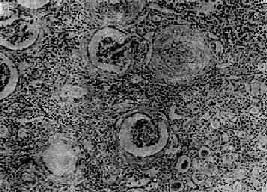

图12-25 慢性肾盂肾炎

有些肾小球毛细血管丛相对正常,肾球囊壁增厚,纤维化,部分肾小管萎缩消失,部分肾小管扩张,腔内有胶样管型;间质纤维组织增生,有大量淋巴细胞等炎细胞浸润×287